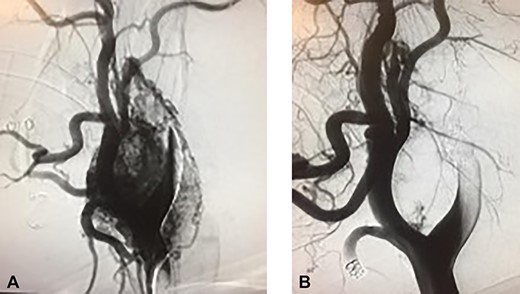

The CBT was nonfunctional and therefore no preoperative alpha blockade was needed. The patient underwent preoperative angiography and embolization by the interventional radiology team to decrease the risk of intraoperative bleeding given the size (7 cm) and the Shamblin III classification (Fig. 2A and B). The surgery was performed a week later by the surgical oncology team assisted by a vascular surgeon.

Preoperative embolization of CBTs remains a controversial topic. The risks include postembolization morbidity such as transient ischemic attack and even stroke by embolic particles [6].

The inflammatory effects of preoperative embolization could make precise subadventitial dissection more difficult. Benefits of preoperative embolization include decrease of tumor size facilitating complete resection and decreased blood loss. Currently, embolization seems to be beneficial for tumors larger than 5 cm, Shamblin’s type III, and those with significant cranial extension [7]. Correlation between preoperative embolization and vascular reconstruction has not been established.